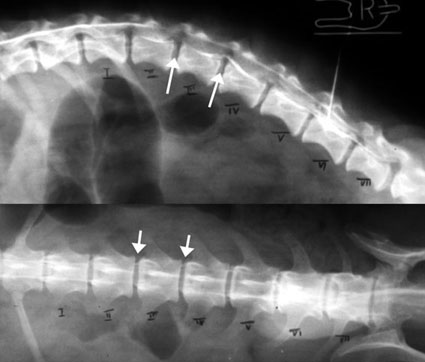

ハンセンII 型の椎間板ヘルニア症

6歳齢、体重5kgのミニチュアダックスフント。

約1か月前に背部痛と歩行時のふらつきで来診し、内科治療で改善していました。

手術前日から立てなくなり、神経学的検査でも強い麻痺徴候が見られました。脊髄造影では、第2−第3および第3−第4腰椎間の左側に強い脊髄圧迫が認められ、とくに第3−第4腰椎間は重度でした。

写真上段: 脊髄造影X線写真

上半分は側面像、下半分は腹背像。白矢印で示した部位で造影剤の白いラインが消えたり押し上げられており、、脊髄が圧迫されているのがわかります。

写真中段: 脊髄造影X線写真

左半分は左下斜め像、右半分は右下斜め像。

左下斜め像ので圧迫像(白矢印)が強く出ていることから、左側で椎間板ヘルニアが起こっていることがわかります。